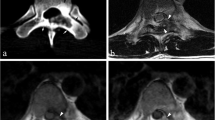

Examples of tumor shape. A- Smooth shape seen in a midline located chordoma of the sacrum with intraspinal-extraspinal extension on T2 fat-saturated MR image. B- Lobulated shape seen in an eccentrically located chondrosarcoma of the mobile spine with intraspinal-extraspinal extension on T2 fat-saturated MR image

Smooth margins occurred in the majority of skull base tumors (15/23 patients, 65.2%), especially among chordomas, in accordance with the prevalence of the histological diagnosis. (Table 2) As lobulated margins at the skull base were found in four patients with chordoma (4/8 patients, 50.0%) and in four chondrosarcoma patients, it was thus, relative to the histologic prevalence, more common in chondrosarcomas.

In the mobile spine, smooth margins were most common (13/21 patients, 61.9%), but were not present in the two chondrosarcomas.

Also in the sacrum, smooth margins were most common (21/36 patients, 58.3%), and seen in almost all histological diagnoses. Most patients had, in accordance with the histological prevalence, chordoma. (Fig. 5A) All four patients with GCTB had, as in the mobile spine, smooth margins. Lobulated margins were almost exclusively seen in chordomas (13/15 patients, 86.7%), only one chondrosarcoma and one osteosarcoma patient also had lobulated margins. (Fig. 5B).

Examples of signal intensity. A- Heterogenous hyperintensity seen on T2-weighted MRI sequence in a midline located chordoma of the sacrum with extraspinal extension. B- Homogeneous hyperintensity seen on T2-weighted MRI sequence in chondrosarcoma of the skull base. C- Hypointensity seen on T2-weighted MRI sequence in a midline located sacral giant cell tumor of the bone with intraspinal extension

Signal Intensity (SI)

Predominantly hyperintense areas were visible on T2-weighted MR sequences in the majority of patients (74/80 patients, 92.5%), independent of histology and location. (Table 2) These areas appeared heterogeneous in 49 patients (Fig. 6A); distributed over chordomas (39/49 patients, 79.6%), GCTB (4/49 patients, 8.2%), chondrosarcoma (3/49 patients, 6.1%), and one each of osteosarcoma, plasmacytoma and Ewing sarcoma. These hyperintense areas appeared homogenous in the remaining 25 patients who had plasmacytoma (5/25 patients, 20.0%), chondrosarcoma (9/25 patients, 36.0%) (Fig. 6B), chordoma (9/25 patients, 36.0%) or GCTB (2/25 patients, 8.0%). Hypointense areas on T2-weighted sequences were seen in five tumors only; two of these were GCTB (Fig. 6C), and one each was chondrosarcoma, osteosarcoma and plasmacytoma. Isointensity was seen in only one patient with osteosarcoma.